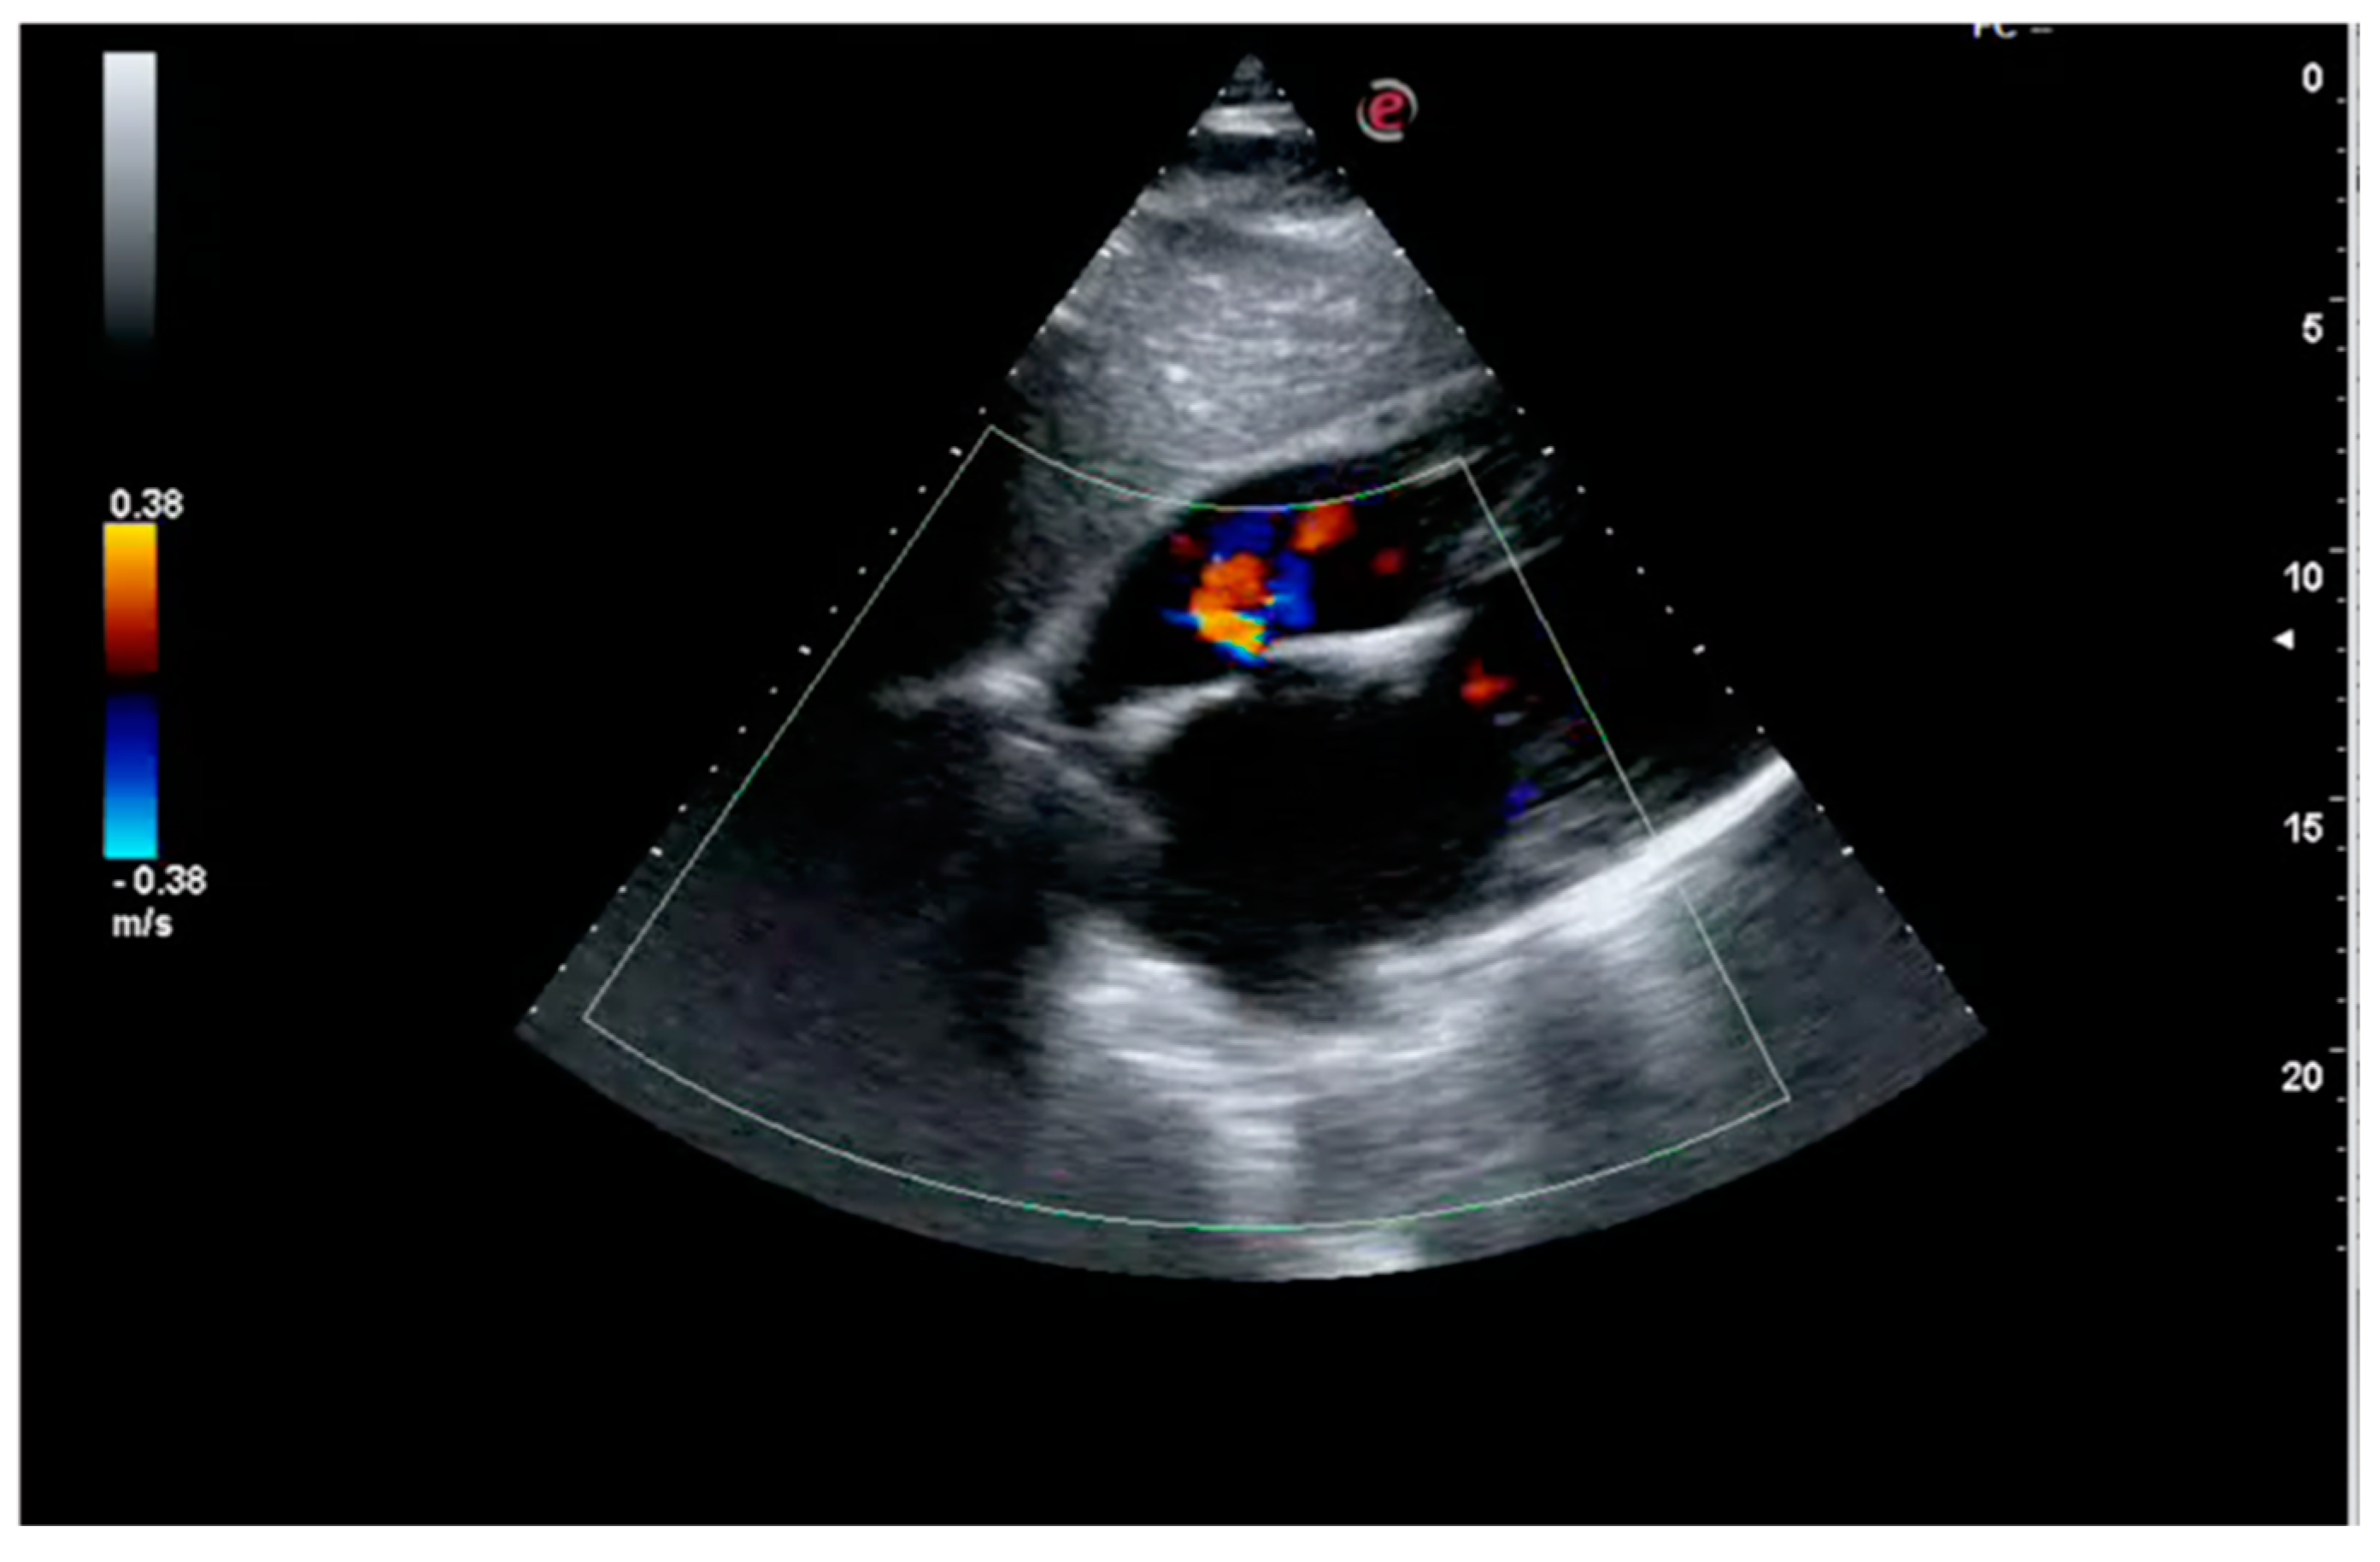

1. Case Report

2. Case Discussion

2.3. Iatrogenic Interatrial Septal Defect, In Situ Thrombosis and Paradoxical Embolism